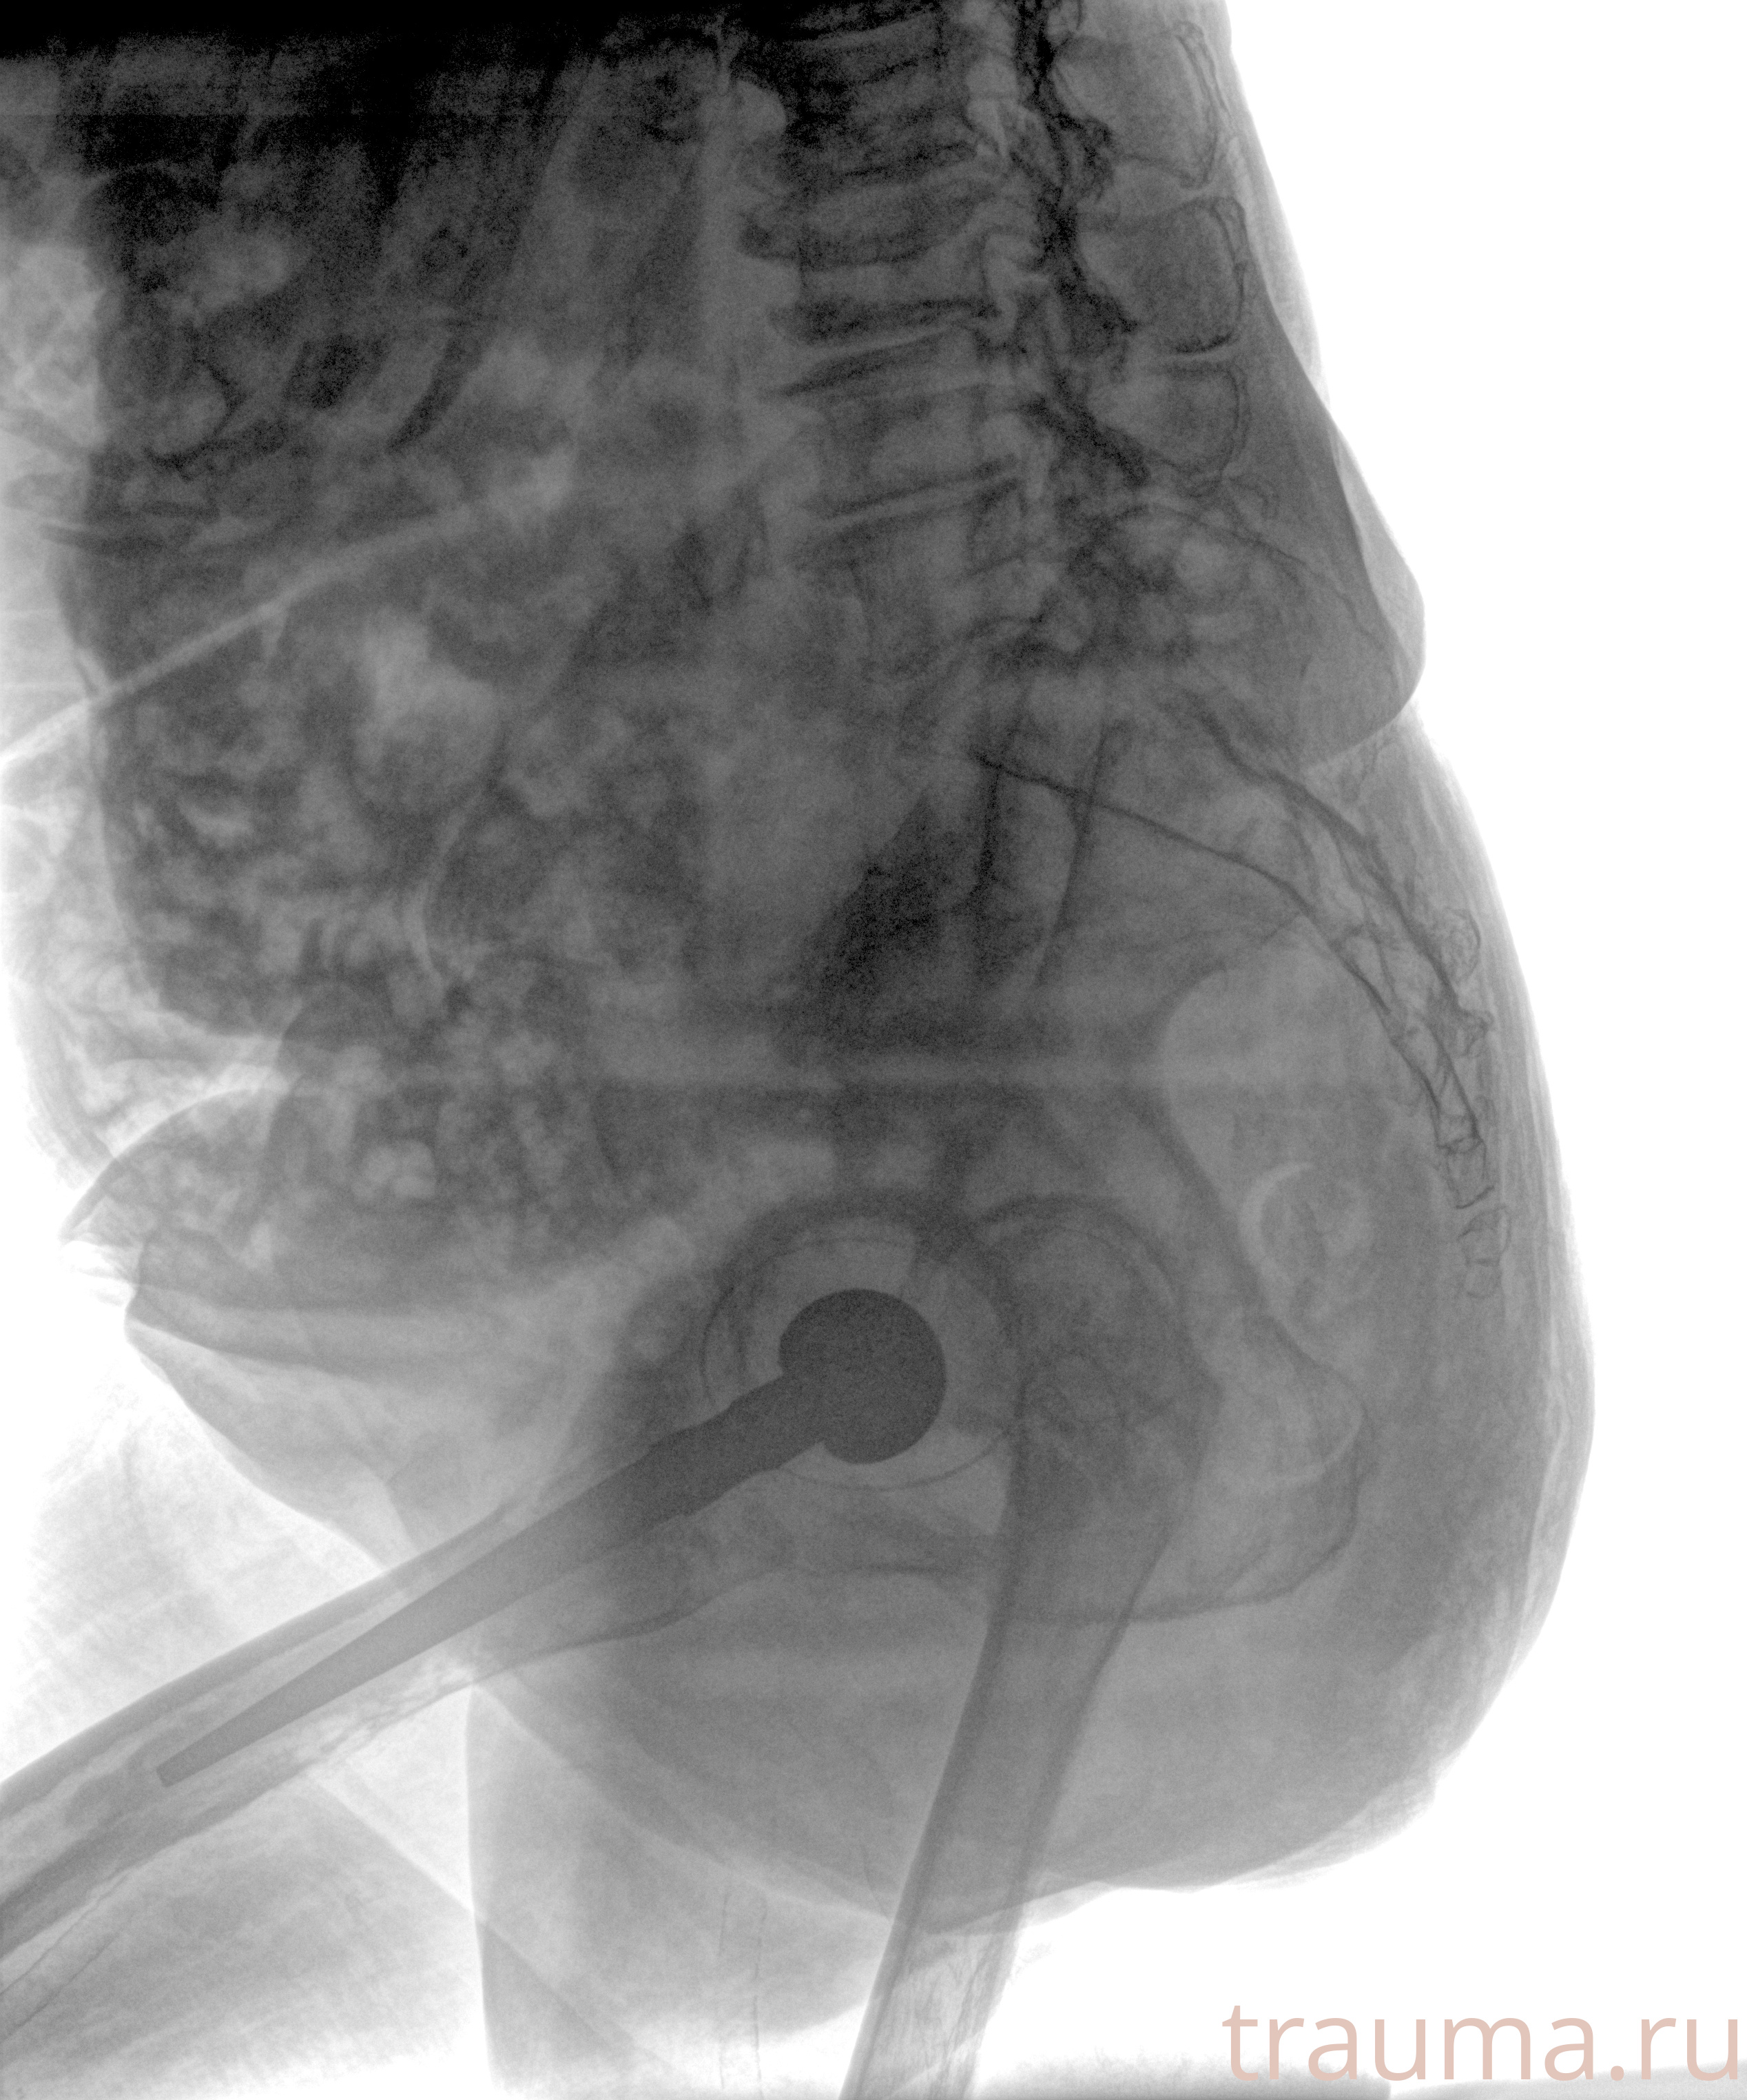

Рентген на дому: по вашему адресу приезжает врач-рентгенолог, травматолог-ортопед с мобильным рентгеновским аппаратом, проводит диагностику травмы или заболевания, делает необходимые рентгенограммы, дает рекомендации по дальнейшему лечению. Получить качественные снимки в домашних условиях возможно благодаря уникальной методике, разработанной МосРентген Центром для института  Склифосовского